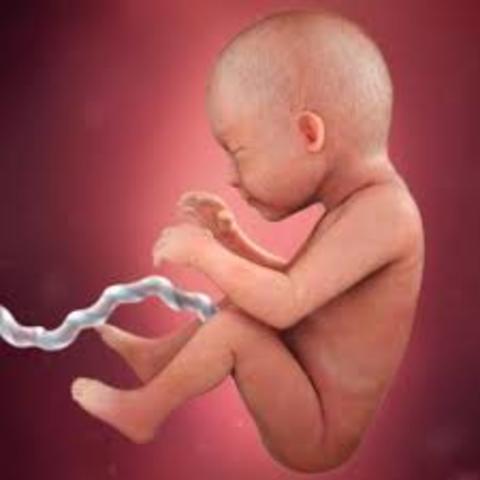

The fetus now weighs approximately 5 ounces and is 5 inches in length (9 inches stretching out). The umbilical cord is stronger and thicker and its' retinas are becoming sensitive to light. Also, stool is starting to form as well.